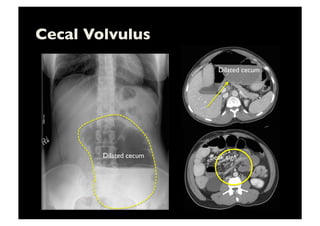

Cecal Volvulus

Dilated cecum

Beak sign